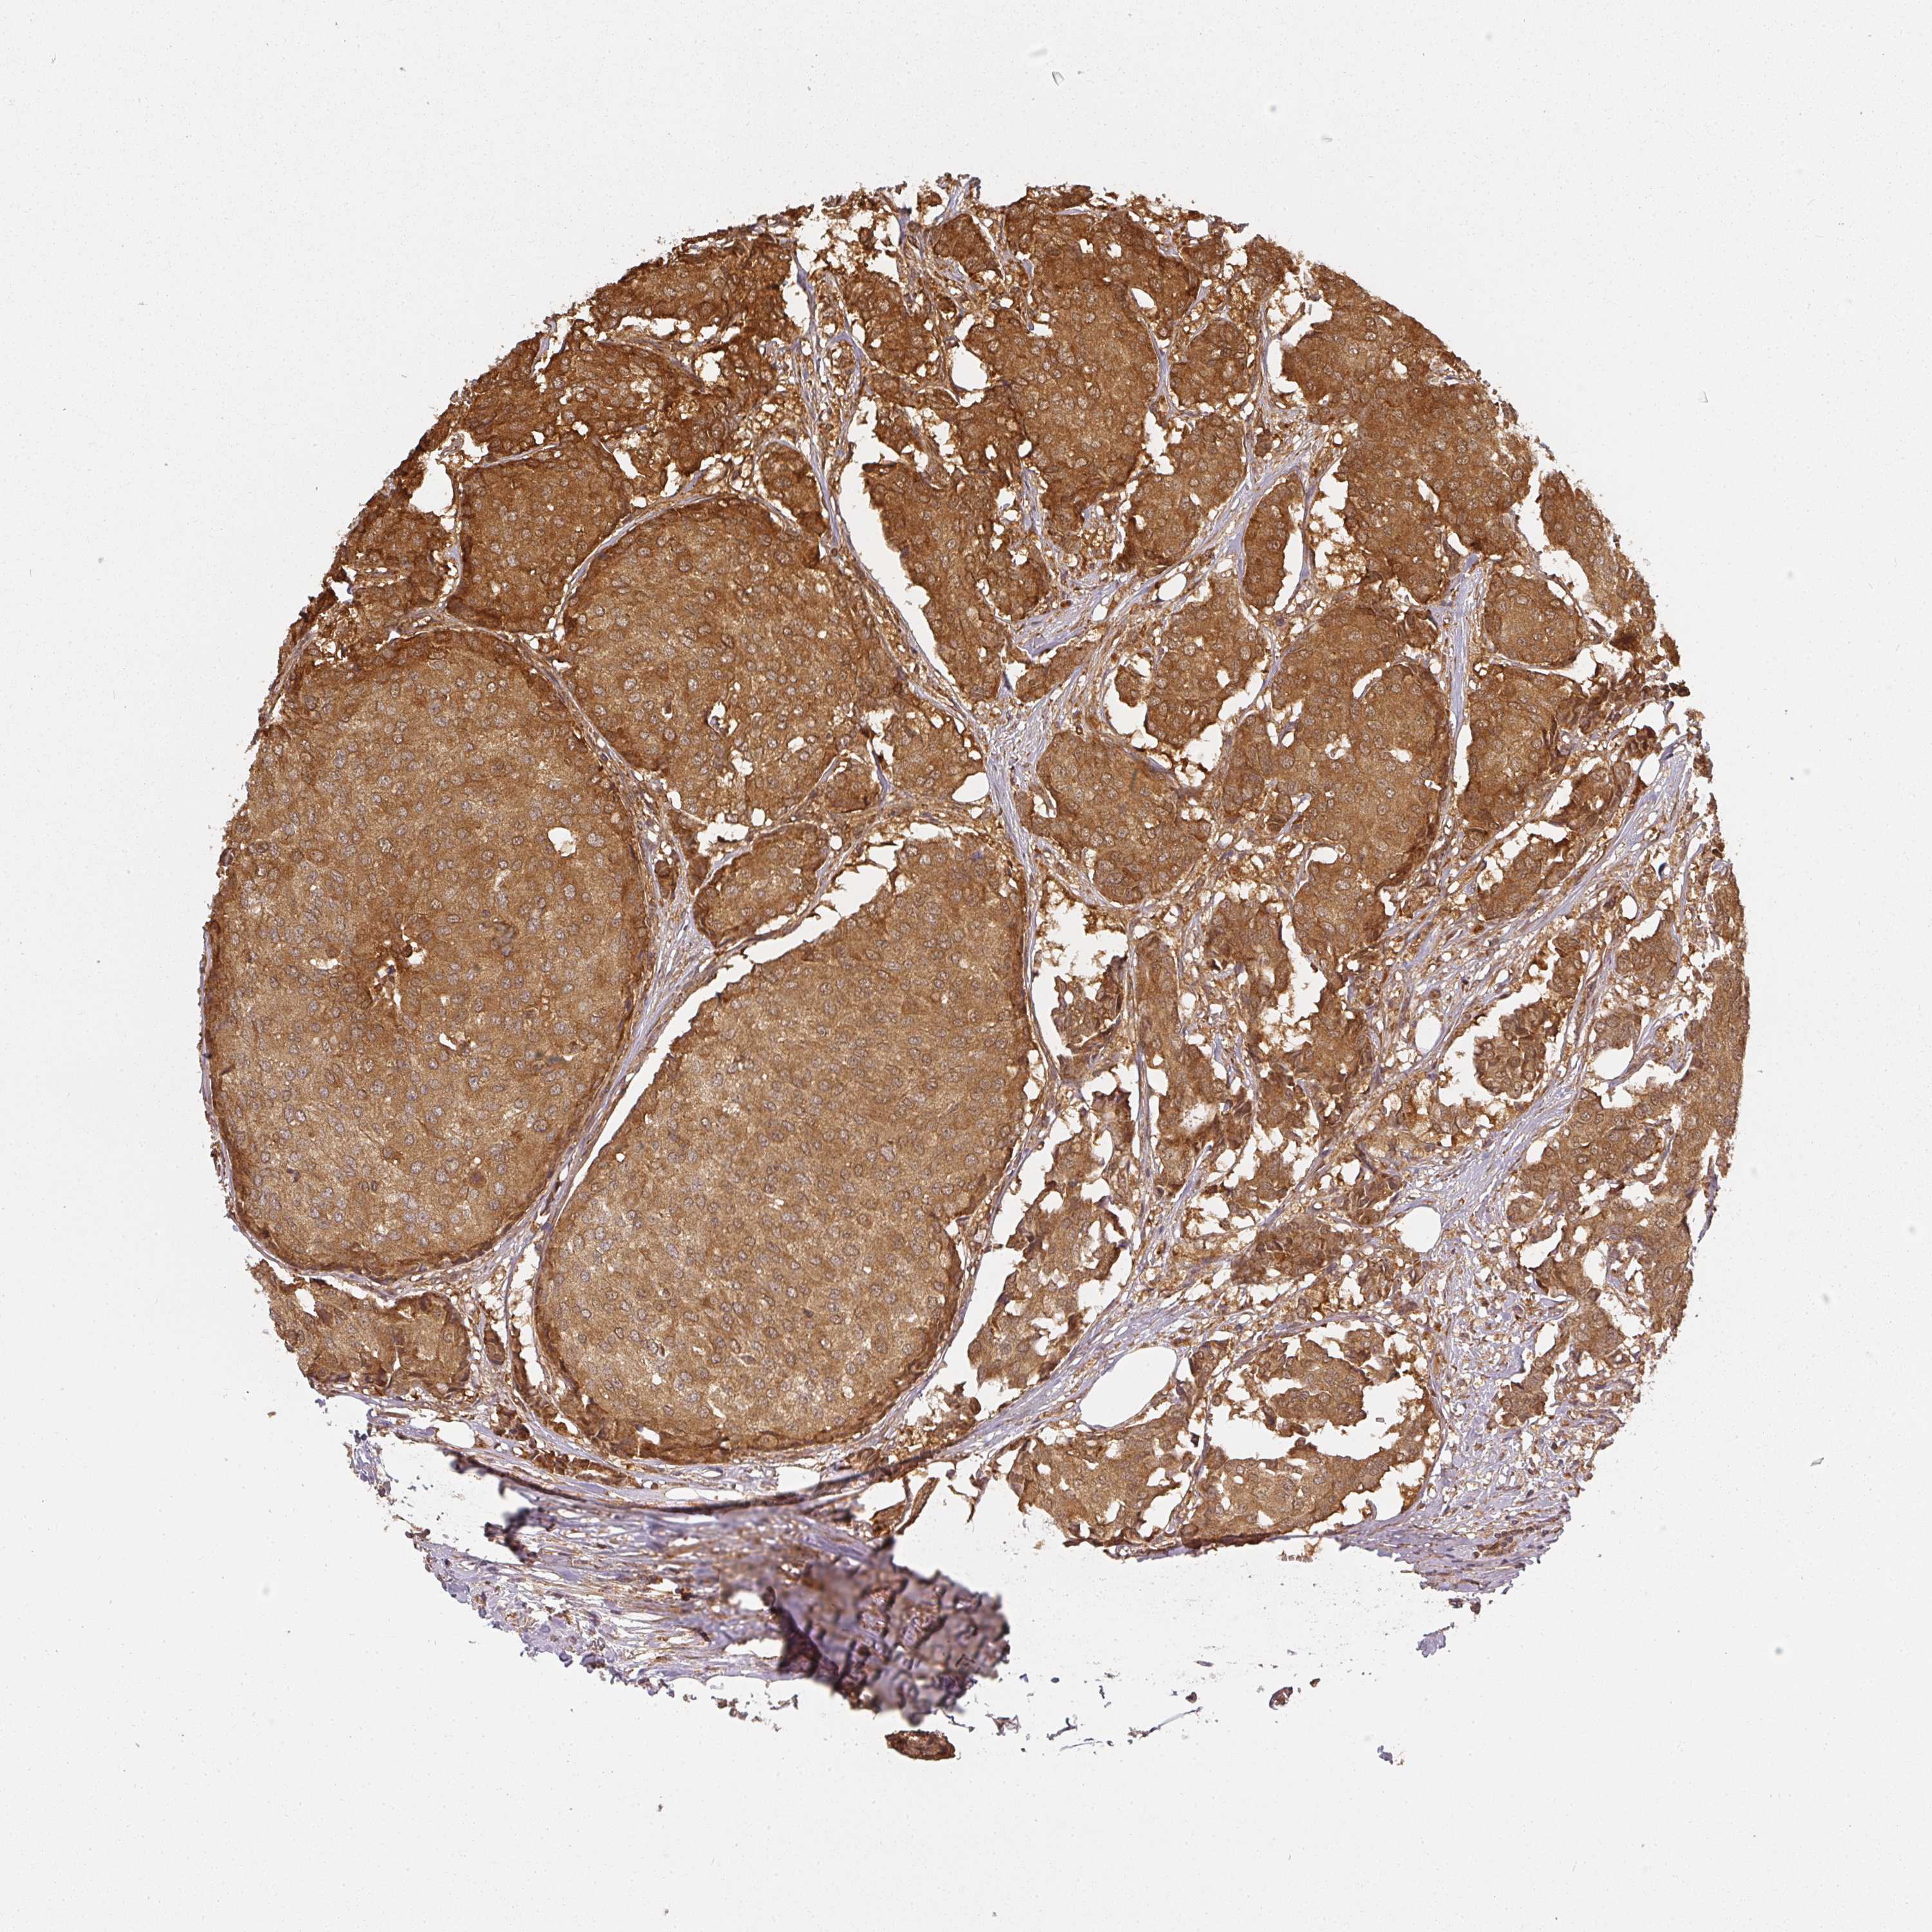

BRCA TCGA BRCA VALIDATION PROTEIN EXPRESSION

ANTIBODIES

AND

VALIDATION